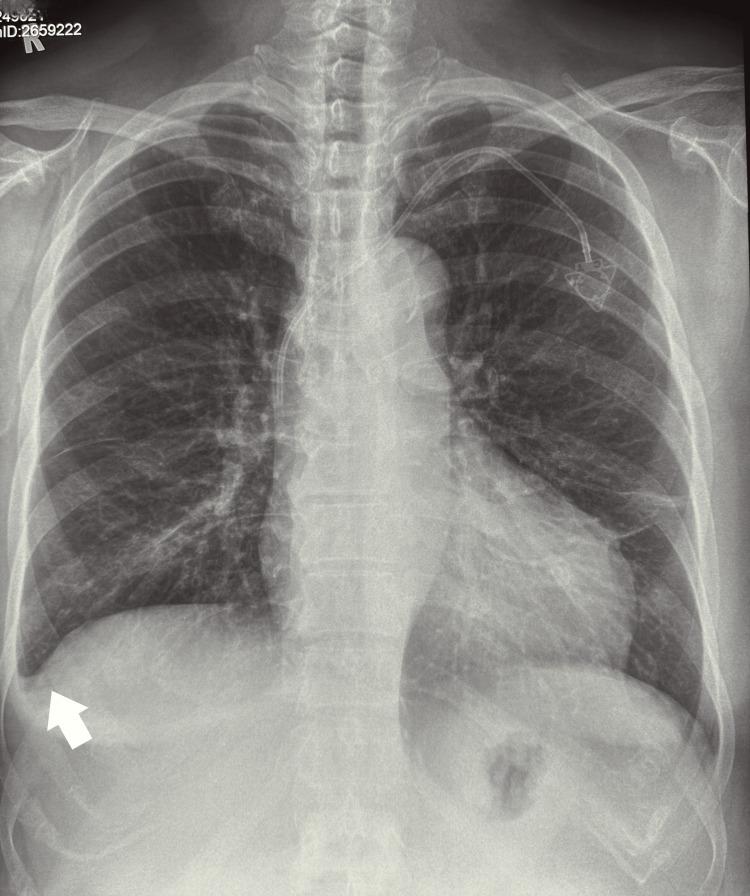

A 67-year-old woman presented to a chiropractor with a four-week history of neck and low back pain, lower extremity paresthesia, profound fatigue, and cutaneous pallor. Previous cervical radiographs had revealed multilevel degenerative spondylosis. However, abnormal hematological indices, including severe thrombocytopenia and anemia, prompted concerns of an underlying hematopoietic malignancy. Interdisciplinary collaboration facilitated expedient hematological assessment, confirming acute lymphoblastic leukemia (ALL), as evidenced by lymphoblasts in a peripheral blood smear and bone marrow biopsy. Karyotyping detected a Philadelphia chromosomal mutation; the patient therefore received oral targeted tyrosine kinase inhibition coupled with serial intrathecal chemotherapy. Complete remission was achieved. However, sensorimotor symptoms persisted due to herpetic neuralgia secondary to immunosuppression. This complex case underscores the role of chiropractors as primary contact clinicians in identifying sinister pathologies underlying musculoskeletal complaints via judicious history-taking, physical evaluation, and interpretation of investigational findings. Interprofessional collaboration is pivotal in formulating an effective therapeutic strategy to improve the prognosis of patients with this disease.

一名67岁女性因颈部和下背部疼痛、下肢感觉异常、极度疲劳和皮肤苍白等症状持续四周,前来就诊于一名脊椎按摩师。先前的颈椎X光片显示有多节段退行性脊柱病。然而,包括严重血小板减少症和贫血在内的异常血液学指标引发了对潜在造血系统恶性肿瘤的担忧。跨学科合作促成了快速的血液学评估,确诊为急性淋巴细胞白血病(ALL),外周血涂片和骨髓活检中的原始淋巴细胞证实了这一诊断。核型分析检测到费城染色体突变;因此,该患者接受了口服靶向酪氨酸激酶抑制治疗并辅以鞘内化疗。实现了完全缓解。然而,由于免疫抑制继发的疱疹性神经痛,感觉运动症状持续存在。这个复杂的病例强调了脊椎按摩师作为初级接诊临床医生的作用,即通过审慎的病史采集、体格检查和对检查结果的解读,识别肌肉骨骼症状背后的隐匿病变。跨专业合作对于制定有效的治疗策略以改善该疾病患者的预后至关重要。